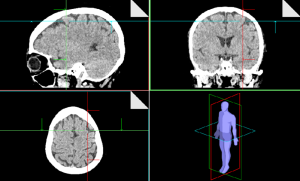

É inegável que os exames de imagem tiveram um papel essencial no trabalho do Dr. Ryke Geerd Hamer. Foi por meio das tomografias que ele identificou os chamados “Focos de Hamer”, áreas cerebrais que se correlacionam com programas biológicos específicos. Esses achados foram decisivos para as relações evolutivas feitas pelo Dr Hamer e o desenvolvimento tão refinado e preciso do conhecimento que hoje chamamos de 5 Leis Biológicas.

Na prática, alguns terapeutas ainda orientam seus clientes a realizar a tomografia e enviá-la para especialistas (às vezes até em outros países) para obter uma “leitura”. Além de uma exposição à radiação desnecessária (que apresenta riscos), há todo o custo envolvido, o limite de competência de quem solicita e na aplicação prática, isso se torna demorado, já que pode levar semanas até que a análise retorne; esse processo não corresponde ao que ensinava o próprio Hamer.

As imagens, quando analisadas isoladamente, não substituem a presença viva do cliente, suas palavras, seus gestos e a riqueza de sinais orgânicos que se manifestam no momento da consulta. Além disso, o quadro de uma pessoa pode mudar rapidamente, e aquilo que aparecia no exame no dia da captura, pode já não estar configurado da mesma forma alguns dias depois.

Outro ponto a ser considerado é que a leitura de tomografias é complexa. Mesmo médicos radiologistas enfrentam dificuldades nessa interpretação. Tentar reduzir a compreensão dos processos biológicos a uma leitura fria de imagem, sem a experiência clínica direta, pode levar a equívocos e até a interpretações que mais confundem do que ajudam.